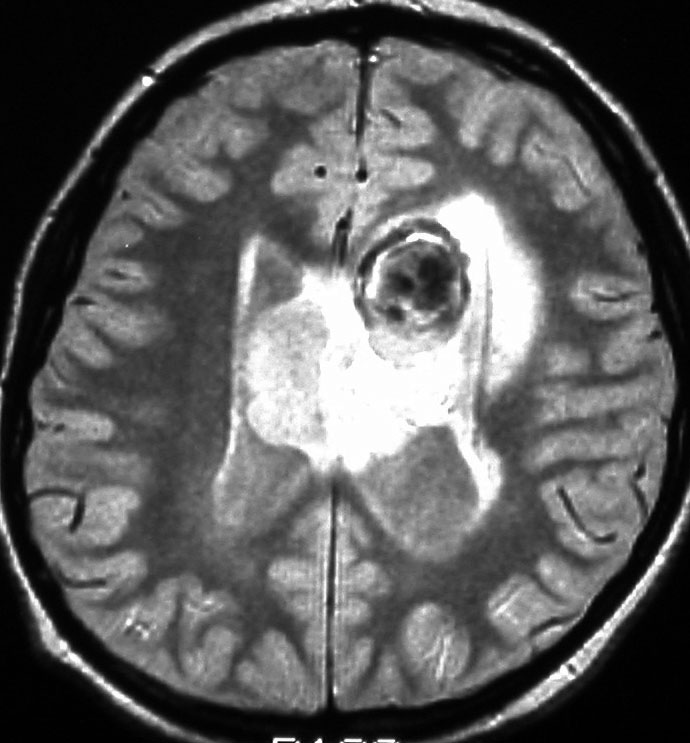

症候性の大きなSEGA

水頭症で発症した10歳の男の子のSEGAです。左側脳室の前角という部位から発生しました。腫瘍は右の脳室にものう胞を形成して,両側のモンロー孔を塞いだために閉塞性水頭症になって,頭痛と嘔吐が出ました。腫瘍の前方には腫瘍内出血もあります。

経皮質法 transcortical approachで摘出した後のMRI画像です。手術中には腫瘍からの出血は多く,深い位置にあり脳質壁を損傷しないように全摘出するのは難しいものでした。その後10年以上たっていますが再発していません。

この例は結節性硬化症を伴わないものでした。